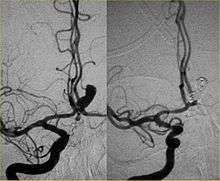

The technique that constitutes the basis for angiographic neurointerventions, and thus, interventional neuroradiology, was first developed in 1927 by the Portuguese physician Egas Moniz at the University of Lisbon to provide contrasted x-ray angiography in order to diagnose several kinds of nervous diseases, such as tumors, coronary heart disease and arteriovenous malformations. He is usually recognized as one of the pioneers in this field. Moniz performed the first cerebral angiogram in Lisbon in 1927.